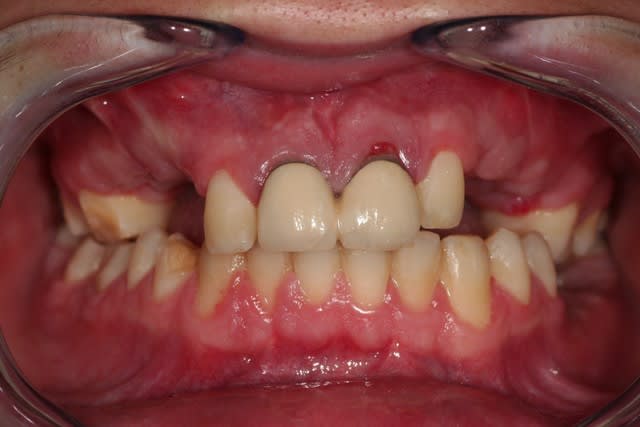

Vue generale déf pzjqut - Eugenol

alhoun

11/07/2007 à 21h13

pardonnez les quelques excès de ciment!!

et pour ceux qui n'ont pas envie de retourner au début...

Initial eqcrc5 - Eugenol

Une question de novice,est ce parce que les couronnes de 15,24 et 25 sont sur implants qu'elles sont plus "rentrées" que les autres? impossible de récupérer le bombé de l'arcade comme avec des ceramiques sur couronnes?

je te jure alhoun, ce n'est pas une critique (beau travail) mais une information pour une non "implanteuse" (tiste?)

12/07/2007 à 12h33

et quand bien même ce serait une critique...

non, les prémols sont dans leur position d'origine, c'est le genre de sourire qu'avait le patient...nous avons repositionné les canines par rapport à d'anciennes photos, et je crois que c'est ça qui donne cet effet.

là ou j'ai ce genre de problème, par contre, c'est en 36 et 37. malgré des extractions complètement atraumatiques, si ce mot peut être employé sur ce cas précis, il y a eu perte osseuse, et je suis légèrement lingualé.